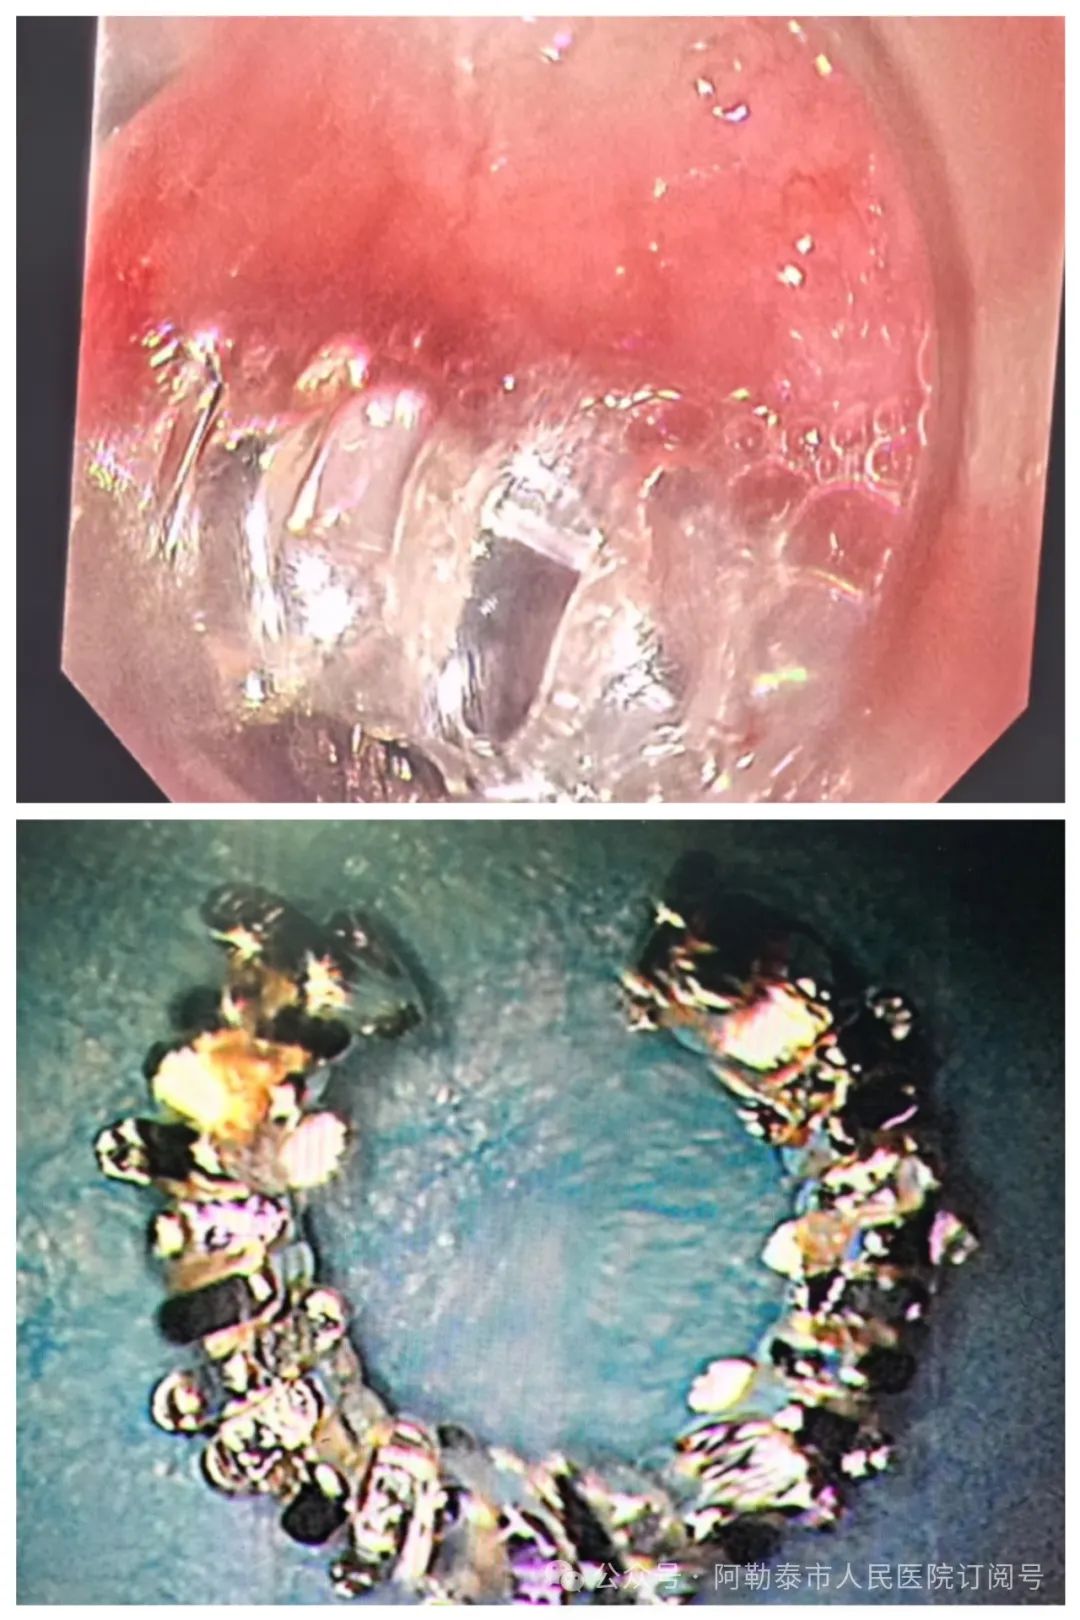

当天,两位焦急万分的家长怀抱哭闹不止的婴儿紧急转院至阿勒泰市人民医院。经询问得知,宝宝在玩耍时不慎将耳环放入口中,导致耳环嵌顿在食管,随即出现呻吟、哭闹和烦躁不安等症状。家长发现后,第一时间带孩子前往当地医院,当地医院排片明确诊断为食管上段环形齿轮状异物,建议转至阿勒泰市人民医院就诊。

接诊后,钟强明副院长迅速组织科内会诊。在充分讨论并再次进行影像学检查后,医疗团队明确了异物的位置、大小、形态以及与周边脏器的关系,同时排除了食管穿孔及出血等并发症,确诊为“食管异物”。考虑到患儿年龄太小,情况危急,若不及时取出异物,极有可能引发食管黏膜水肿、缺血、穿孔、出血等危及生命的严重并发症,医疗团队决定立即实施异物取出术。

然而,摆在面前的困难重重。患儿食管狭小,普通内镜难以通过并抵达异物处;婴儿无法配合手术,且因无牙齿无法咬住咬口器,哭闹不停;加之年龄过小,麻醉风险极大。面对诸多挑战,阿勒泰市人民医院消化内科团队精心筹备并制定应急预案。最终,在无需麻醉的情况下,钟强明副院长凭借精湛医术,应用奥林巴斯超细胃镜,成功取出异物。整个过程仅用时几分钟,且未对患儿食管黏膜造成任何损伤,无出血、穿孔等并发症发生。